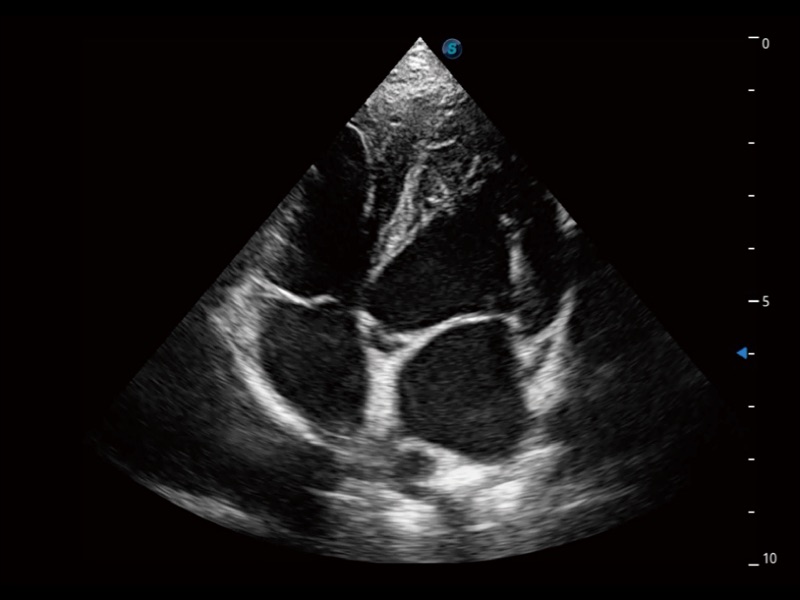

能夠基于左心室壁追蹤和辛普森法,自動(dòng)計(jì)算射血分?jǐn)?shù),支持多個(gè)可移動(dòng)點(diǎn)描跡,與手動(dòng)測(cè)量相比,極大節(jié)省了動(dòng)物醫(yī)生的時(shí)間和精力。